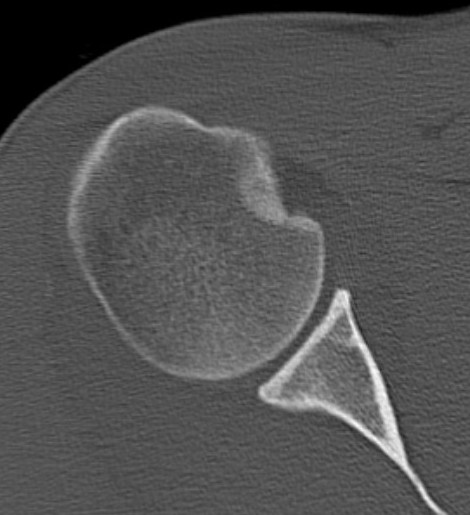

CT scan

Confirms dislocation

Reverse Hill Sachs

Humeral head defect

- caused by impaction of anterior humeral head on posterior glenoid

- intra-articular

- measured as a percentage of the articular surface

Lesser tuberosity fractures

Posterior glenoid fractures / bony bankart